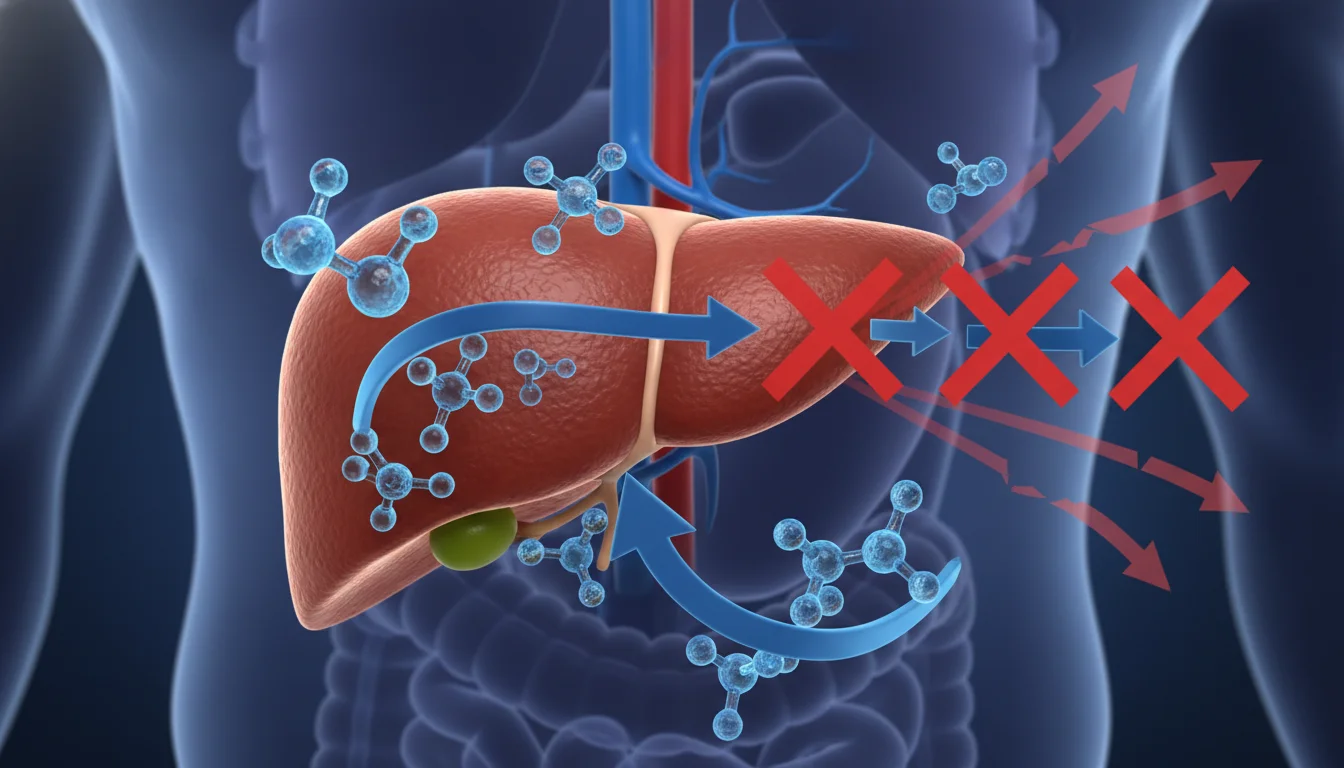

Quando um diabético consome cerveja, ocorre um efeito duplo e perigoso: os carboidratos da bebida causam um pico rápido e imediato na glicose, enquanto o álcool inibe a capacidade do fígado de liberar açúcar no sangue, podendo gerar uma crise grave de hipoglicemia horas depois.

Para entender esse mecanismo, é preciso olhar para o fígado. Este órgão vital funciona como um grande reservatório de energia para o corpo humano.

Em situações normais, quando a glicose no sangue começa a cair — seja pelo uso de insulina, seja pelo tempo em jejum, o fígado realiza um processo chamado gliconeogênese, liberando glicose para manter o sistema equilibrado.

No entanto, o corpo humano enxerga o álcool como uma toxina. Assim que a primeira dose entra na corrente sanguínea, o fígado prioriza a metabolização e a eliminação dessa substância química, interrompendo abruptamente a sua função de liberar glicose.

- Gliconeogênese: processo vital no qual o fígado produz e libera glicose a partir de outras substâncias (como aminoácidos) para manter o corpo funcionando durante o jejum. É exatamente este processo que o álcool paralisa.

Como o fígado lida com o álcool e o diabetes simultaneamente?

O fígado não consegue realizar ambas as funções ao mesmo tempo. Ao detectar álcool no sangue, ele abandona a função de liberar glicose para processar e eliminar as toxinas da bebida alcoólica, desregulando completamente a homeostase do corpo do diabético.